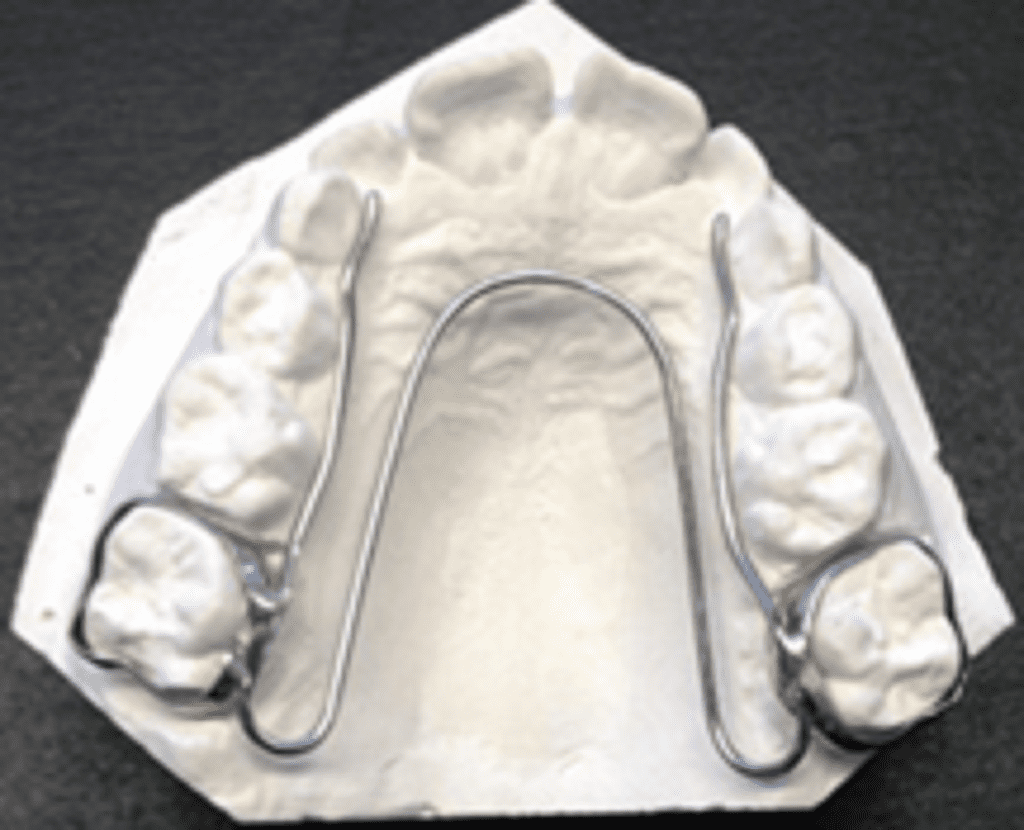

d) W-arch appliance

The W-arch appliance was introduced by Ricketts 1975.

Appliance framework Constructed with 0.036-inch stainless steel wire. Wire is adapted to the form of ‘W’ which extends from the first permanent molar to the canine in the anterior palate. Free ends of the ‘W’ are adapted closely to the palatal surfaces of premolars/deciduous molars. Appliances should be away from the palatal mucosa to prevent tissue irritation. Lingual arch is soldered to bands on molars. The finished appliance is cemented to the first permanent molars.

Activation

- For anterior expansion – opening of apices of ‘W’ (position 2)

- For posterior expansion – opening near anterior region (position 1)

The appliance delivers proper force levels if opened 4–5 mm wider than the passive width and should be adjusted to this dimension before being inserted. The appliance is activated at the rate of 2mm per month until the cross bite is mildly overcorrected.